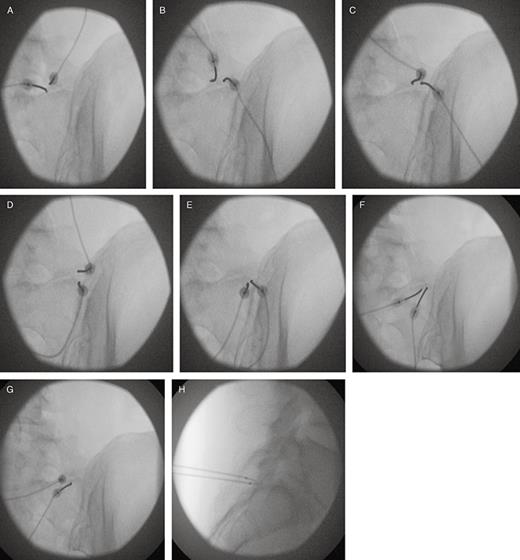

1705283463147.png

Case report of it.

View attachment 381015